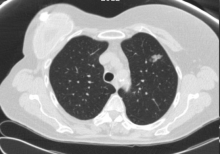

A 70-year-old woman with a past history of breast cancer in 2004 also had a nonperipheral pseudonodular ground glass appearance lesion in the left upper lobe since 2010, a core-needle biopsy in 2012 and 2015, and a diagnosis of benign pneumocytoma (Figure 1). Since 2018, the lesion had a growth of the solid component in chest computed tomography scan, so a positron emission tomography scan was performed, which showed an increased metabolic uptake in the lesion (SUV max 2.77) (Figure 2).

Figure 2